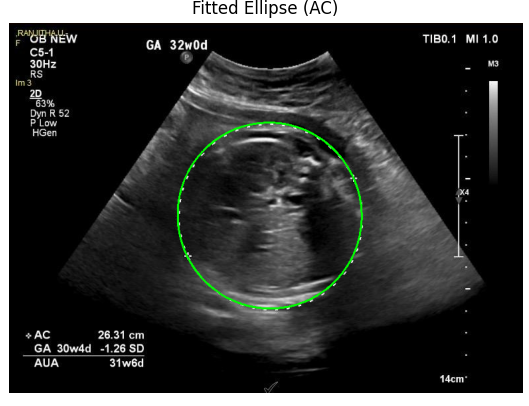

Managed and preprocessed over 10,000 ultrasound images for fetal report generation.

Co-developed healthcare reports that automate fetal health and nutrition analysis.